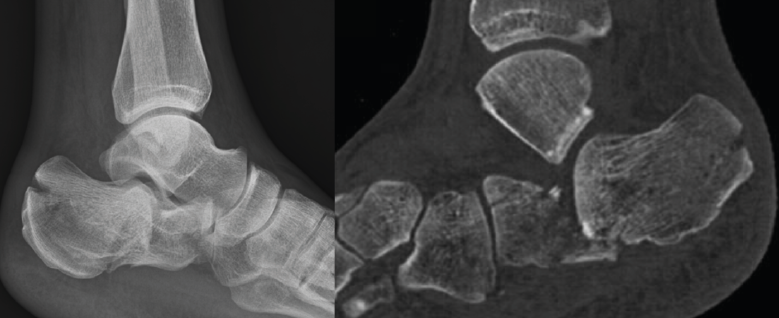

Radiológicamente, se evaluó la reducción conseguida, mediante la medición del ángulo de Böhler poscirugía, y el mantenimiento de dicha reducción midiendo dicho ángulo a los 3 meses poscirugía. El ángulo de Böhler(21) se mide en una radiografía lateral del tobillo tomando la intersección de una línea trazada desde la cara superior de la tuberosidad del calcáneo posterior a la superficie articular subastragalina superior y una línea trazada desde la superficie articular subastragalina superior a la cara superior del proceso anterior del calcáneo (Figura 1). Se considera este ángulo dentro de la normalidad cuando se obtienen unos ángulos entre 20 y 40°, siendo los ángulos < 20° sugerentes de fractura.

Figura 3. Varón de 59 años con fractura del calcáneo de Sanders de tipo IIA tras caída de 2 m de altura. Ángulo de Böhler precirugía de 6,3°, ángulo de Böhler poscirugía de 20,7° y a los 3 meses de 22,3°. No presentó ninguna complicación.

Figura 5. Varón de 37 años con fractura del calcáneo de Sanders de tipo IIB tras caída de altura. En la imagen de la tomografía computarizada se observa hundimiento de la zona lateral de la subastragalina posterior y un trazo posterior “en lengua”. Ángulo de Böhler precirugía de 8,5°.